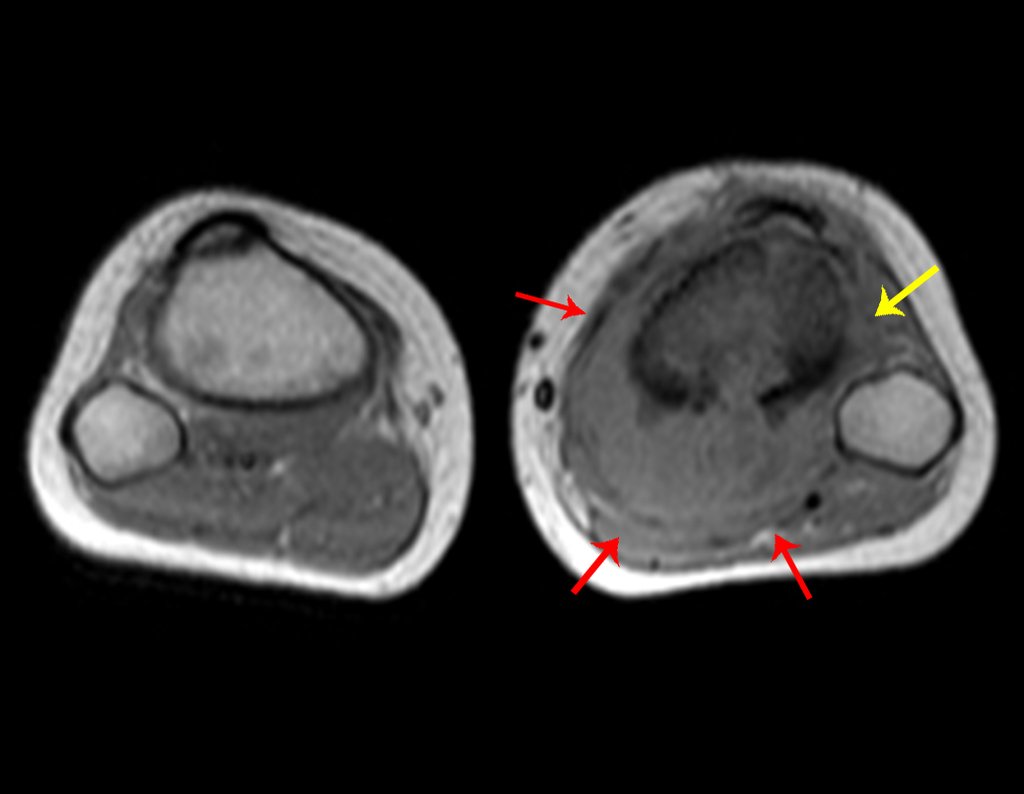

Ingresó en el hospital en mayo y se sometió a una biopsia por punción. El informe anatomopatológico indicó osteosarcoma central convencional localizado, con cultivos negativos. Se le realizó estadificación con TC de tórax, gammagrafía ósea de todo el cuerpo y resonancia magnética del miembro inferior derecho. Se le realizaron tres ciclos de quimioterapia neoadyuvante con Platino y Doxorrubicina, con buena respuesta.